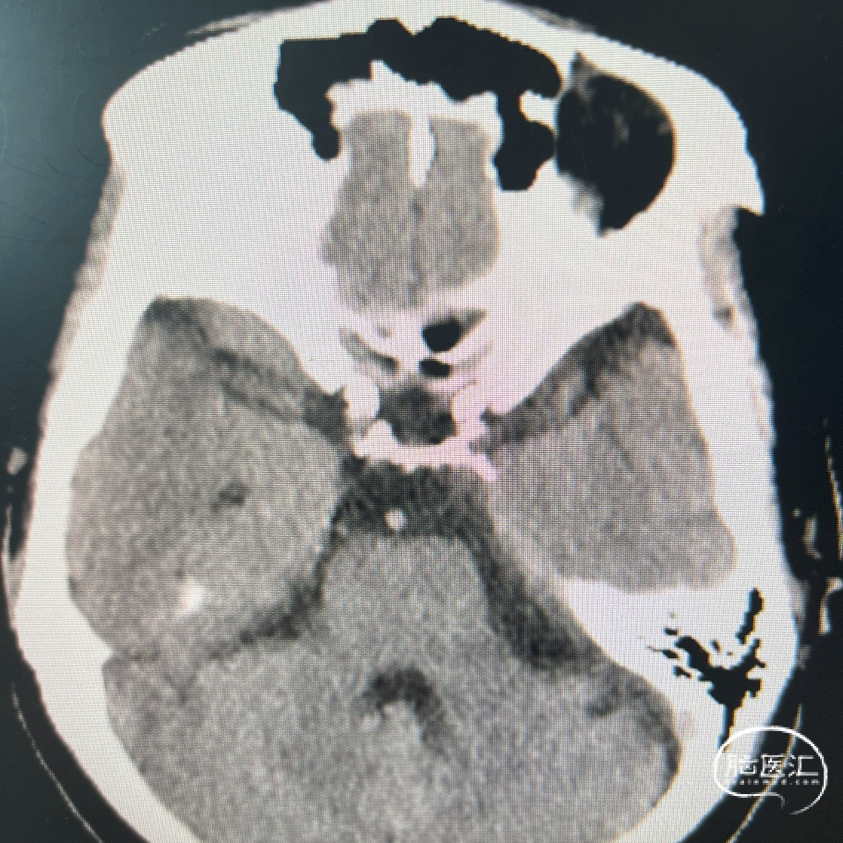

影像学表现:

1、主动脉弓及其他弓上血管,III型弓,弓上血管迂曲,血管通畅。

2、颈内动脉系统:

右侧颈总动脉及颈内动脉血管通畅,远端右侧大脑中动脉血流通畅,可见同侧及对侧大脑前动脉显影。

左侧颈总动脉及颈内动脉血流通畅,后交通开放,可见同侧大脑后动脉显影,大脑前动脉血流通畅。

3、椎基底动脉系统:

右侧椎动脉优势型。

左侧椎动脉血管纤细,远端可见基底动脉浅淡显影。

右侧椎动脉优势型,远端汇入基底动脉。

基底动脉中段重度狭窄,狭窄率约80%,双侧大脑后动脉可见显影。